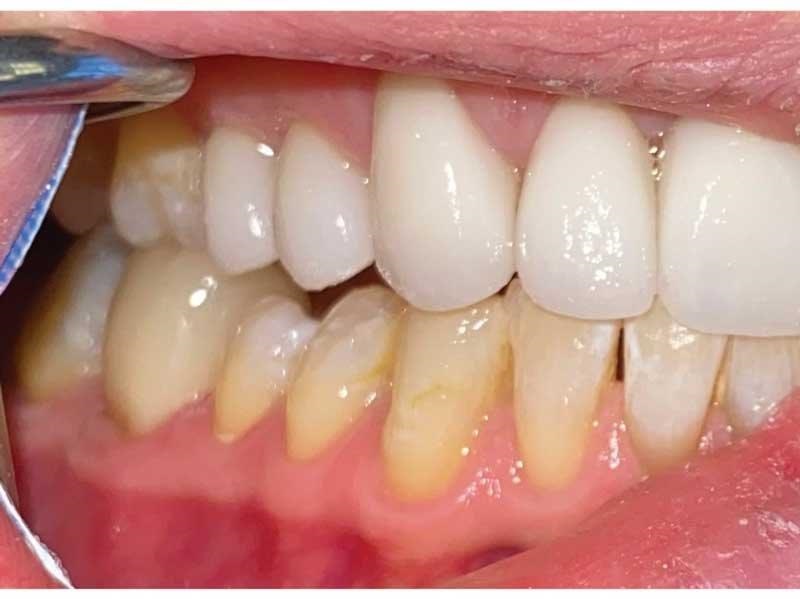

Meet Lorraine, who came into my office to “redo her bonding.” Lorraine had some upper anterior teeth done years ago with resin, which now was dull, stained and breaking down (Figs. 1–3). She had an amount of money in mind that she thought it would cost. She was very wrong.

Fig. 1

Fig. 2

Fig. 3